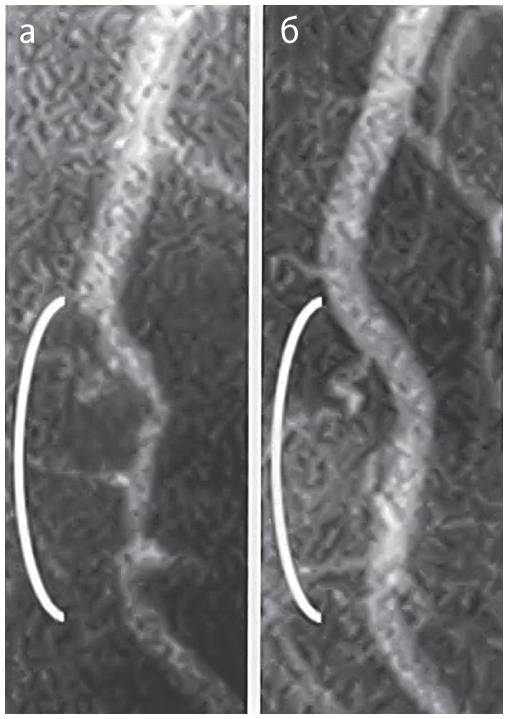

Один врач-терапевт обратил особое внимание на исследование Эссельстина. Ему было всего 44, и он, казалось, был здоров, когда внезапно обнаружил, что у него имеются проблемы с сердцем, приведшие к инфаркту миокарда. Ввиду природы сердечно-сосудистых заболеваний традиционная медицина не могла предложить ему надежного решения проблемы. Он обратился к Эссельстину и решил принять участие в программе лечения, предусматривавшей соблюдение диеты. Спустя 32 месяца, без применения каких-либо медикаментов, понижающих уровень холестерина в крови, течение его болезни повернулось вспять, а уровень холестерина в крови снизился до 2,3 ммоль/л. Большое впечатление производит снимок больной артерии этого пациента до и после выполнения диетических предписаний Эссельстина (рис. 5.4) {332}. Светлые участки на рисунках – это кровь, протекающая через артерию.

Рис. 5.4. Коронарная артерия до и после соблюдения растительной диеты

На рисунке слева (а) имеется участок, помеченный круглой скобкой, где серьезная ишемическая болезнь привела к сокращению кровотока. После соблюдения диеты, основанной на цельных растительных продуктах, та же артерия открылась, губительное действие ишемической болезни обернулось вспять и кровоток практически нормализовался, как видно на рисунке справа (б).